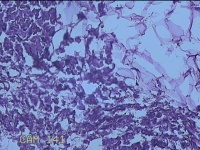

外阴部包块

性别

女

年龄

37岁

临床诊断

皮脂腺囊肿

一般病史

外阴部起包块一月余。

标本名称

大体所见

灰白暗红色包块2.3x1.8x0.8cm一个,表面糜烂,切开包块呈实性,切面灰白淡黄色,质软。

有那么点像脂肪瘤。